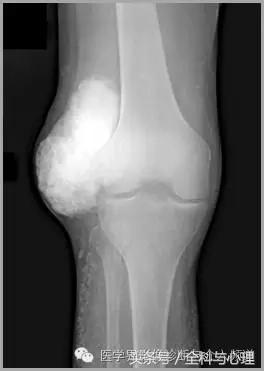

五、滑膜软骨瘤病

1°少见,病灶数量多,大小均匀,相邻关节正常。

2°多见,病灶数量少,大小不一,多伴有退行性骨关节病。

滑膜骨软骨瘤病 1°

滑膜骨软骨瘤病 2°